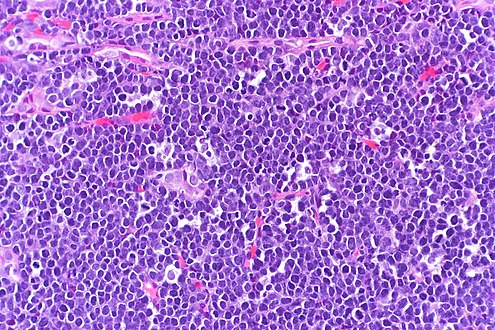

The tumor consists of sheets of a monotonous (i.e., similar in size and morphology) population of medium-sized lymphoid cells with high proliferative and apoptotic activity. The "starry sky" appearance seen[21] under low power is due to scattered tingible body-laden macrophages (macrophages containing dead apoptotic tumor cells). The old descriptive term of "small non-cleaved cell" is misleading. The tumor cells are mostly medium in size (i.e., tumor nuclei size similar to that of histiocytes or endothelial cells). "Small non-cleaved cells" are compared to "large non-cleaved cells" of normal germinal center lymphocytes. Tumor cells possess small amounts of basophilic cytoplasm with three to four small nucleoli. The cellular outline usually appears squared off.[citation needed]

The tumor cells in Burkitt lymphoma generally strongly express markers of B cell differentiation (CD20, CD22, CD19), as well as CD10 and BCL6. The tumor cells are generally negative for BCL2 and TdT. The high mitotic activity of Burkitt lymphoma is confirmed by nearly 100% of the cells staining positive for Ki67.[22]